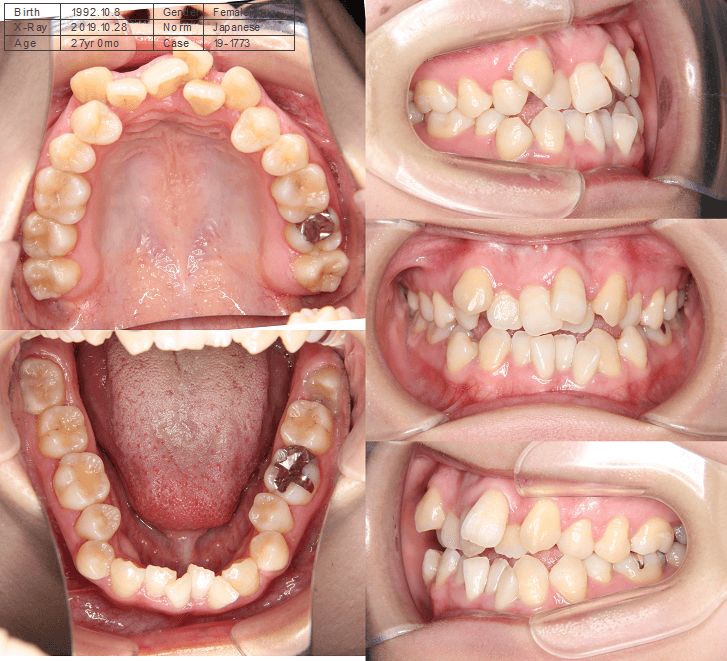

| 年齢・性別 | 25歳の女性 |

|---|---|

| 主訴 | 口元の突出感を気にされて来院された。咬み合わせや審美的な改善を希望されていました。 |

| 治療期間・回数 | 3年6ヶ月・30回 |

| 費用 | 1,000,000円 |